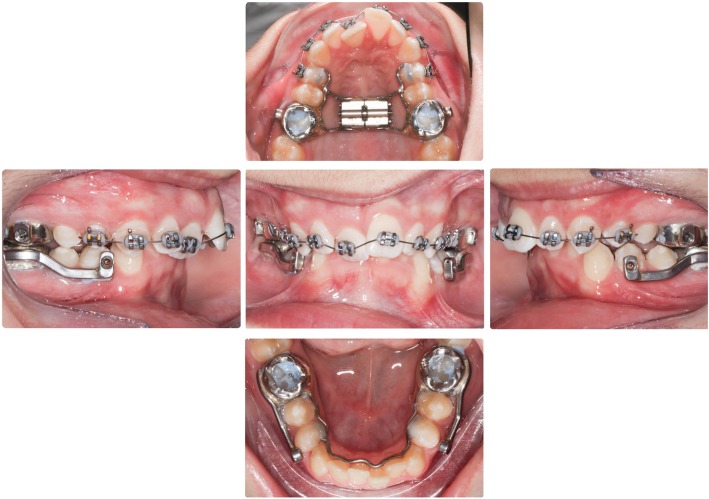

The Herbst appliance consisted of stainless-steel crowns fitted to the maxillary and mandibular first permanent molars and a cantilevered arm extended forwards from the mandibular first molar to the level of the mandibular first premolar. A Hyrax expansion screw appliance connected the maxillary first molars and a 0.040-in. diameter stainless steel lingual arch was used to connect the mandibular first molars (Fig. 1). The mandible was initially advanced 5 mm with subsequent 2 mm advancements to achieve an over-corrected edge-to-edge incisal position. The mean treatment time for the orthopedic phase with the Herbst appliance was 7.79 ± 1.82 months, and the fixed orthodontic phase was 22.08 ± 3.69 months.

Fig. 1.

Intraoral photos of the cantilever Herbst appliance. The Herbst consists of four stainless steel crowns covering the four first molars. A cantilevered arm extended forwards from the mandibular first molar to the level of the mandibular first premolar